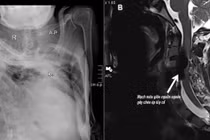

Bơm xi măng sinh học vào cột sống đảm bảo độ vững chắc cho đốt sống. Ảnh BV

Kết quả thăm khám và chẩn đoán hình ảnh cho thấy cụ bị xẹp đốt sống D12 trên nền loãng xương nặng. Đây là bệnh lý phổ biến ở người cao tuổi, đặc biệt là phụ nữ sau mãn kinh; nếu không can thiệp sớm có thể gây biến dạng cột sống, suy giảm vận động và thậm chí tàn phế.

Sau hội chẩn, ê-kíp do BS.CKII Trịnh Văn Phương, Đơn vị Ngoại thần kinh, thực hiện bơm xi măng sinh học (vertebroplasty) để cố định thân đốt sống và giảm đau. Ca can thiệp diễn ra khoảng 30 phút, dưới gây tê tại chỗ. Xi măng sinh học được đưa vào thân đốt sống qua kim dẫn chuyên dụng, giúp tăng độ vững cột sống và giảm áp lực lên cấu trúc thần kinh.